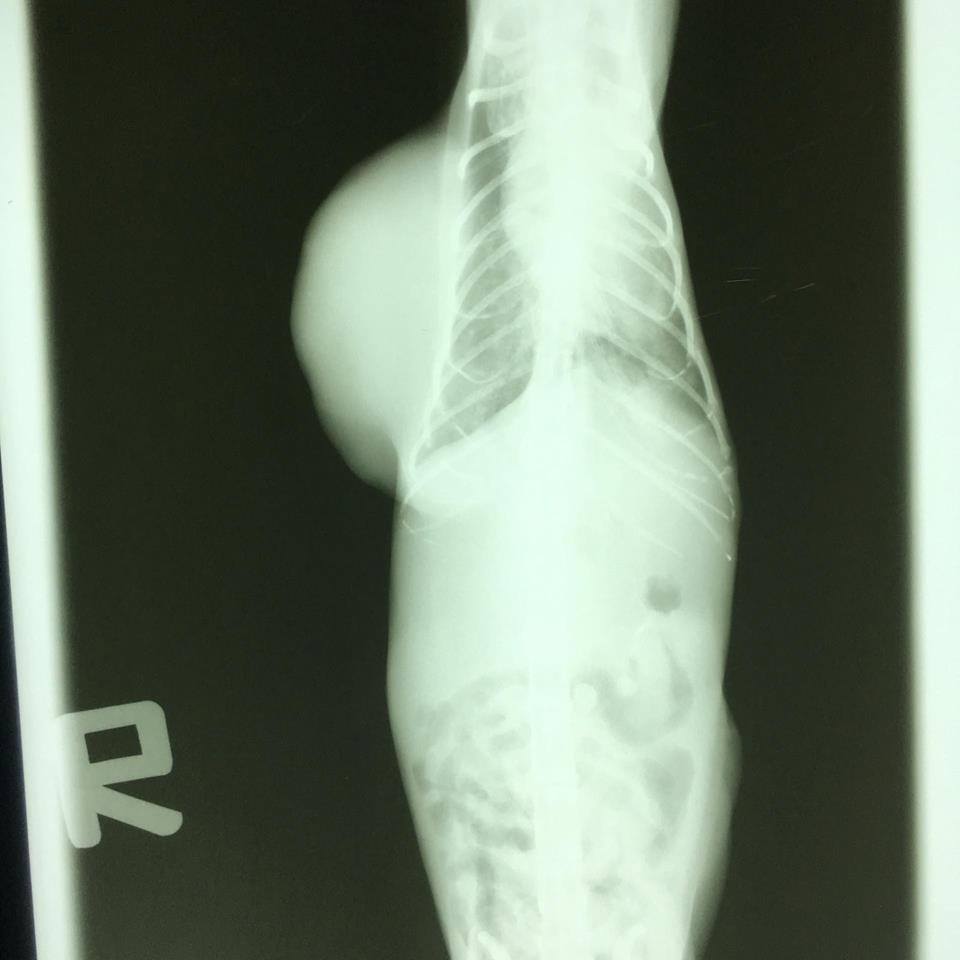

送醫檢查後,

透過X光、超音波觀察,

阿水的腫瘤已經壓迫到脊椎,

也轉移至內臟部份,

已脫水、貧血、嚴重營養不良,

手術已沒意義,

只怕也活不了幾天…